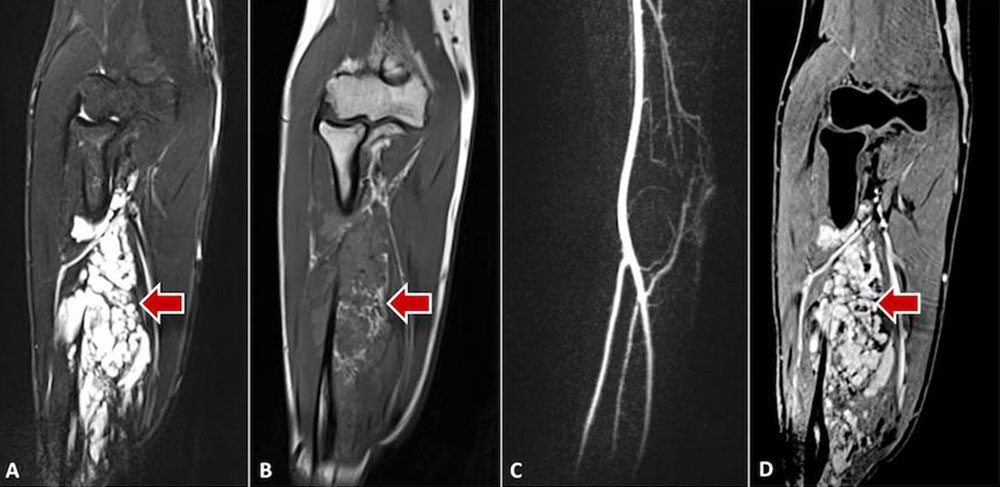

Arteriovenous malformation: The morphologic correlate of the arteriovenous malformation, the so-called nidus (network of direct arteriovenous shunts), is often very hard to detect on native MRI sequences as a solid component is missing in AVMs. Occasionally, the AVM is surrounded by edema or connective and fatty tissue. Typically, spin-echo sequences (T1 or T2) show flow voids within the vessel channels because of high flow velocity. Diagnosis can ultimately be made with the help of dynamic MR angiography with high spatial and temporal resolution. Here, the nidus and the dilated, draining veins are contrasted almost immediately via the corkscrew-like dilated arterial feeders. In lesions located in the extremities, the inflowing and outflowing vessels are usually significantly enlarged compared to the unaffected side. In some cases the vessels are degenerated and show aneurysmal dilatations (so-called flow-related aneurysms). On account of the shunt with low flow resistance, normal vessel sections distal to the shunt may no longer be visible on MRA because of a steal phenomenon. The tissue surrounding the nidus typically does not show contrast enhancement and is hardly recognizable as the actual lesion since the lesion lacks a solid component. However, after invasive procedures or during an inflammatory or proliferative phase, surrounding edema with contrast enhancement is occasionally visible.

13-year-old girl with severe cartilage damage in the knee joint due to extensive peri- and intra-articular venous malformation; therapy with surgical synovectomy and cartilage replacement